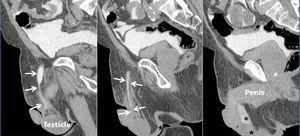

A 76-year-old male with stage 4 CKD secondary to polycystic kidney and liver disease with a long history of high blood pressure, type 2 diabetes mellitus, hyperuricaemia, dyslipidaemia and chronic obstructive pulmonary disease. Given the situation of advanced CKD and after explaining the different dialysis techniques, a straight, non-self-locating 1 cuff peritoneal catheter was inserted by open surgery without immediate incidents, functioning well during the training period. A month after catheter placement, home continuous ambulatory peritoneal dialysis (CAPD) was started with a prescription of 3 exchanges of 2 litres of 1.5% dextrose, initially with neutral or negative balances of 200-300ml. After 4 days of treatment at home, he came to the Peritoneal Dialysis Unit complaining of genital oedema without other associated symptoms. Having performed a testicular ultrasound, pathology was ruled out at this level. On suspicion of leakage, CT peritoneography was carried out, after the administration of 100ml of hypoosmolar iodinated contrast (Optiray® 300mg/ml) by catheter, confirming the passage of peritoneal contrast material through the spermatic cord to the scrotum due to the presence of a non-dilated patent peritoneovaginal duct (Figure 1). Similarly, we observed the existence of a left ipsilateral indirect inguinal hernia with a sac up to 58mm in diameter (Figure 2). Given these findings, peritoneal rest is decided and surgery is indicated for correction of inguinal hernia and closure of the peritoneovaginal duct. With these measures, and after restarting low-volume peritoneal dialysis, no leakage was observed a month after reintervention.

A 45-year-old male with stage 5 CKD secondary to polycystic kidney liver disease with a history of high blood pressure and hyperuricaemia. Given the progressive deterioration of renal function requiring renal replacement therapy, and after explaining the different techniques, a straight, non-self-locating, 1 cuff peritoneal catheter is inserted. A month after starting CAPD at home with 4 exchanges of 2 litres of 1.36% glucose, the patient came to the Peritoneal Dialysis Unit complaining of inguinoscrotal oedema lasting 48 hours. After discarding orchiepididymitis, CT peritoneography was performed as in the previous case, confirming the passage of contrast to the testicles through a patent peritoneovaginal duct. Peritoneal rest was decided and the patient was transferred to haemodialysis. A month later, surgical closure of the peritoneovaginal duct was carried out and CAPD restarted in June 2009 without incident or recurrence of the leakage.

Figure 1. CT peritoneography

Figure 2. CT peritoneography